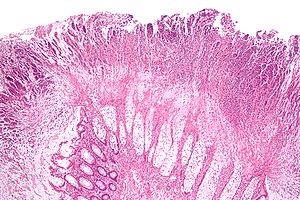

|

Colonic pseudomembrane. H&E stain. | |

Microscopic

Features:[1]

- Heaped necrotic surface epithelium.

- Described as "volanco lesions" - this is what is seen endoscopically.

- PMNs in lamina propria.

- +/-Capillary fibrin thrombi.

Notes:

- Pseudomembranes arise from the crypts.

- Rarely have (benign) signet ring cell-like cells.[6]